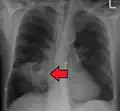

Lung abscesses are often on one side and single involving posterior segments of the upper lobes and the apical segments of the lower lobes as these areas are gravity dependent when lying down. Presence of air-fluid levels implies rupture into the bronchial tree or rarely growth of gas forming organism.

Pulmonary abscess on CXR